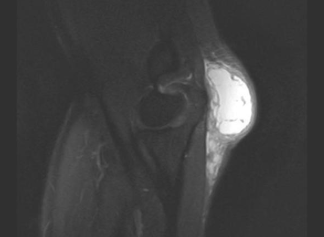

MRI 상 주두 부위로 하얗게보이는 고신호강도의 점액낭염